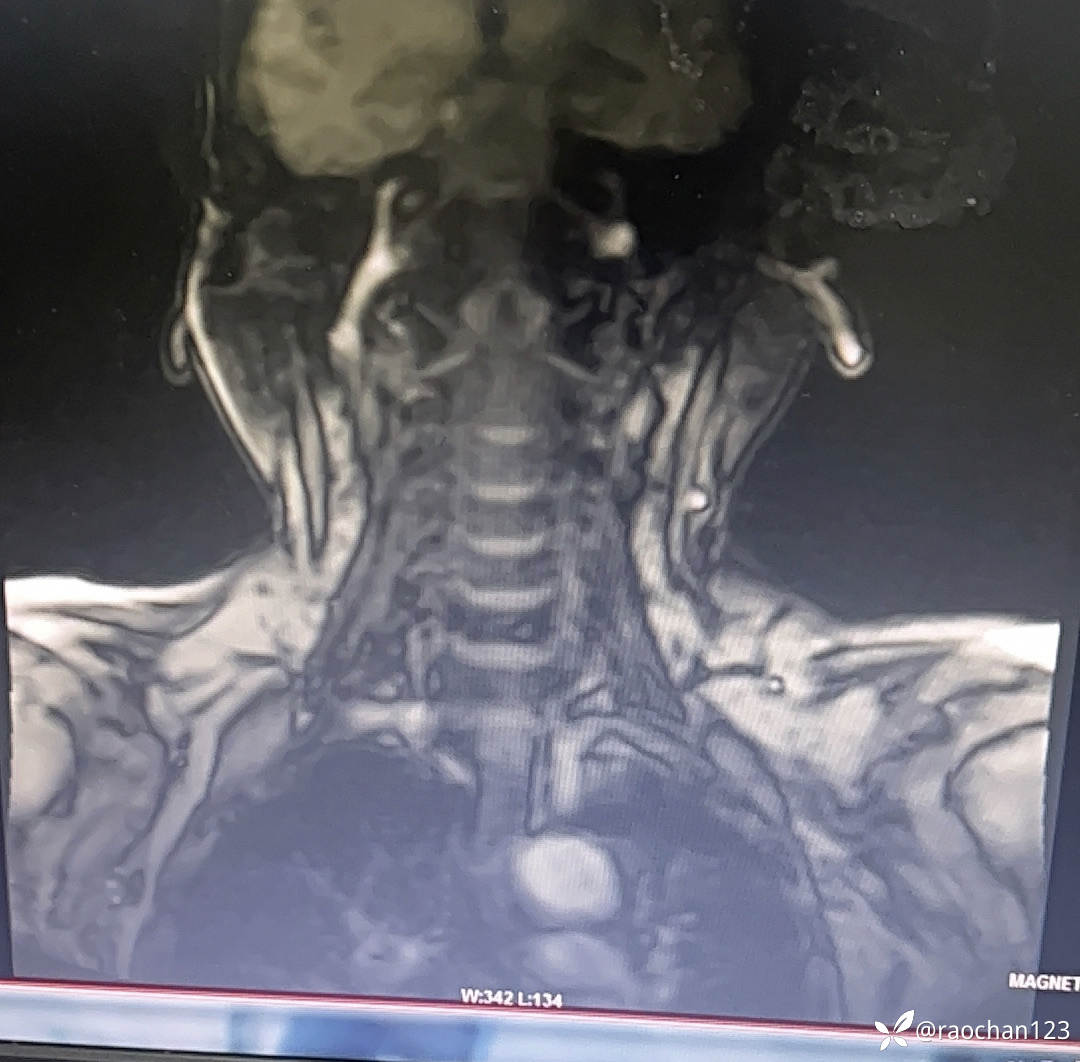

【治疗经过及结果】:给予低流量吸氧,布洛芬混悬液 解热 镇痛,左氧佛沙星抗炎(既往有头孢过敏史)、止痛,热毒宁注射液 清热解毒;艾箱灸、中药塌渍、中药涂擦、火罐、TDP、中药热奄包等中医外治通络祛痛等治疗后,仍有发热,肌酸、肌痛、关节疼痛症状。复查血常规:2024-11-8 13.93# 谷丙转氨酶 45U/L 天门冬氨酸 25U/L 白蛋白 27.0g/L 进一步查乳酸脱氢酶 284U/L 肌酸激酶 26U/L,PCT 0.44ng/ml BNP 811ng/L 免疫五项中IgGA 5.38g/L 血钙 1.94mmol/L 尿微量白蛋白 32.2mg/L 25羟基维生素D 22.68ng/ml 甲胎蛋白、癌胚抗原(-)。颈椎MRI:1.颈椎骨质增生,C4/5、C5/6、C6*7椎间盘轻度突出2、颈后皮下软组织内脂肪堆积,请结合临床。(后颈部皮下软组织内可见异常信号影,T1T2呈高信号,压脂序列呈低信号,颈椎生理曲度变直,椎体后缘连线尚连续,椎体缘骨质光滑,各椎间隙未见狭窄,椎体信号欠均匀,部分椎间盘T2信号减低,C4/5、C5/6、C6/7椎间盘向后轻度突出,硬膜囊轻度受压,椎管无狭窄,黄韧带无肥厚,颈隋未见明显异常)。骨密度:骨质疏松(T值 -4.2)。抗ANA抗体 RF 抗CCP抗体 ENA抗体谱结果待回。患者服用布洛芬混悬液后出现大汗淋漓,血钙偏低,调整为停服布洛芬混悬液、给予醋酸泼尼松10mg 2次/日 口服 解热、抗炎、止痛,金钙尔奇 600mg 2次/日,骨化三醇 0.25ug/日 口服 改善骨质量,暂给予肠内蛋白营养(患者饮食无异常),余治疗同前。